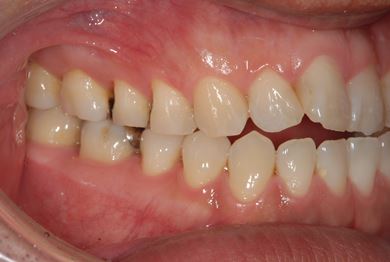

インプラントの症例写真 IMPLANT

インプラント治療

| 性別/年齢 | 男性 / 32歳 | ||||||||||||||||||||||||||||||||

| 主訴 | 銀歯がはずれたところの治療と、インプラント治療相談。 | ||||||||||||||||||||||||||||||||

| 治療方針 | 欠損部分をインプラント治療により、機能的・審美的回復を行う。 | ||||||||||||||||||||||||||||||||

| 治療内容 | インプラント2本、ハイブリッドセラミッククラウン2本 | ||||||||||||||||||||||||||||||||

| 総治療費 | 399,000円 | ||||||||||||||||||||||||||||||||

| 治療期間 | 7ヶ月 |